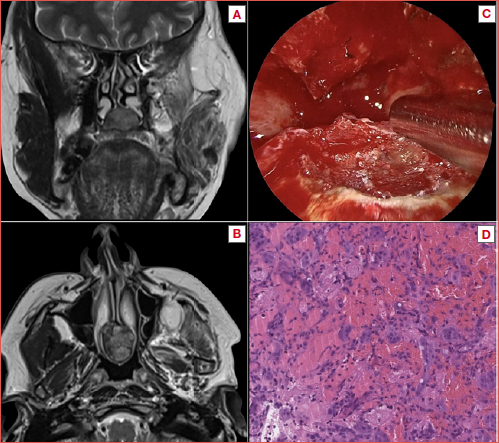

A 45-year-old woman in follow-up with a previous history of a surgically treated GCT of the mandible, had a radiological finding of nasal mass at the contrast-enhanced MRI. She therefore completed the work up with a CBCT and an endoscopic examination: in consideration of the previous medical history, the tumour was classified as a SnGCT of the nasal rostrum with a large root on the nasal floor. The periphery of the lesion appeared hyperostotic, and thus a preoperative biopsy was avoided. The resection of the tumour was completed with a pure endoscopic transnasal approach, with posterior septectomy, and drilling of the basement of the tumour on the nasal floor. The definitive histologic diagnosis was consistent with GCT. The histopathological analysis with routine haematoxylin and eosin stains revealed non-capsulated proliferation of spindle-shaped elements with numerous multinucleated osteoclast-like giant cells, with haemosiderin pigment and haemorrhage, incorporating bone tissue. Immunohistochemical studies were performed with appropriate positive and negative controls. The giant cells were strongly positive for macrophage marker CD68. The patient is free of disease after 4 years of follow-up. Radiological, clinical and histological images of the patient are shown in the Cover figure.

Figure 1. Case 1 from the series. A) CBCT coronal view showing a soft tissue density expansive mass with destructive progression into the palate; B) Contrast-enhanced MRI T2-weighted coronal sequence showing the hypervascularity of the lesion; C) Haematoxylin and eosin stains showing spindle-shaped elements with numerous multinucleated osteoclast-like giant cells, with haemosiderin pigment and haemorrhage, incorporating bone tissue; D) Immunohistochemistry: the giant cells were strongly positive for macrophage marker CD68.